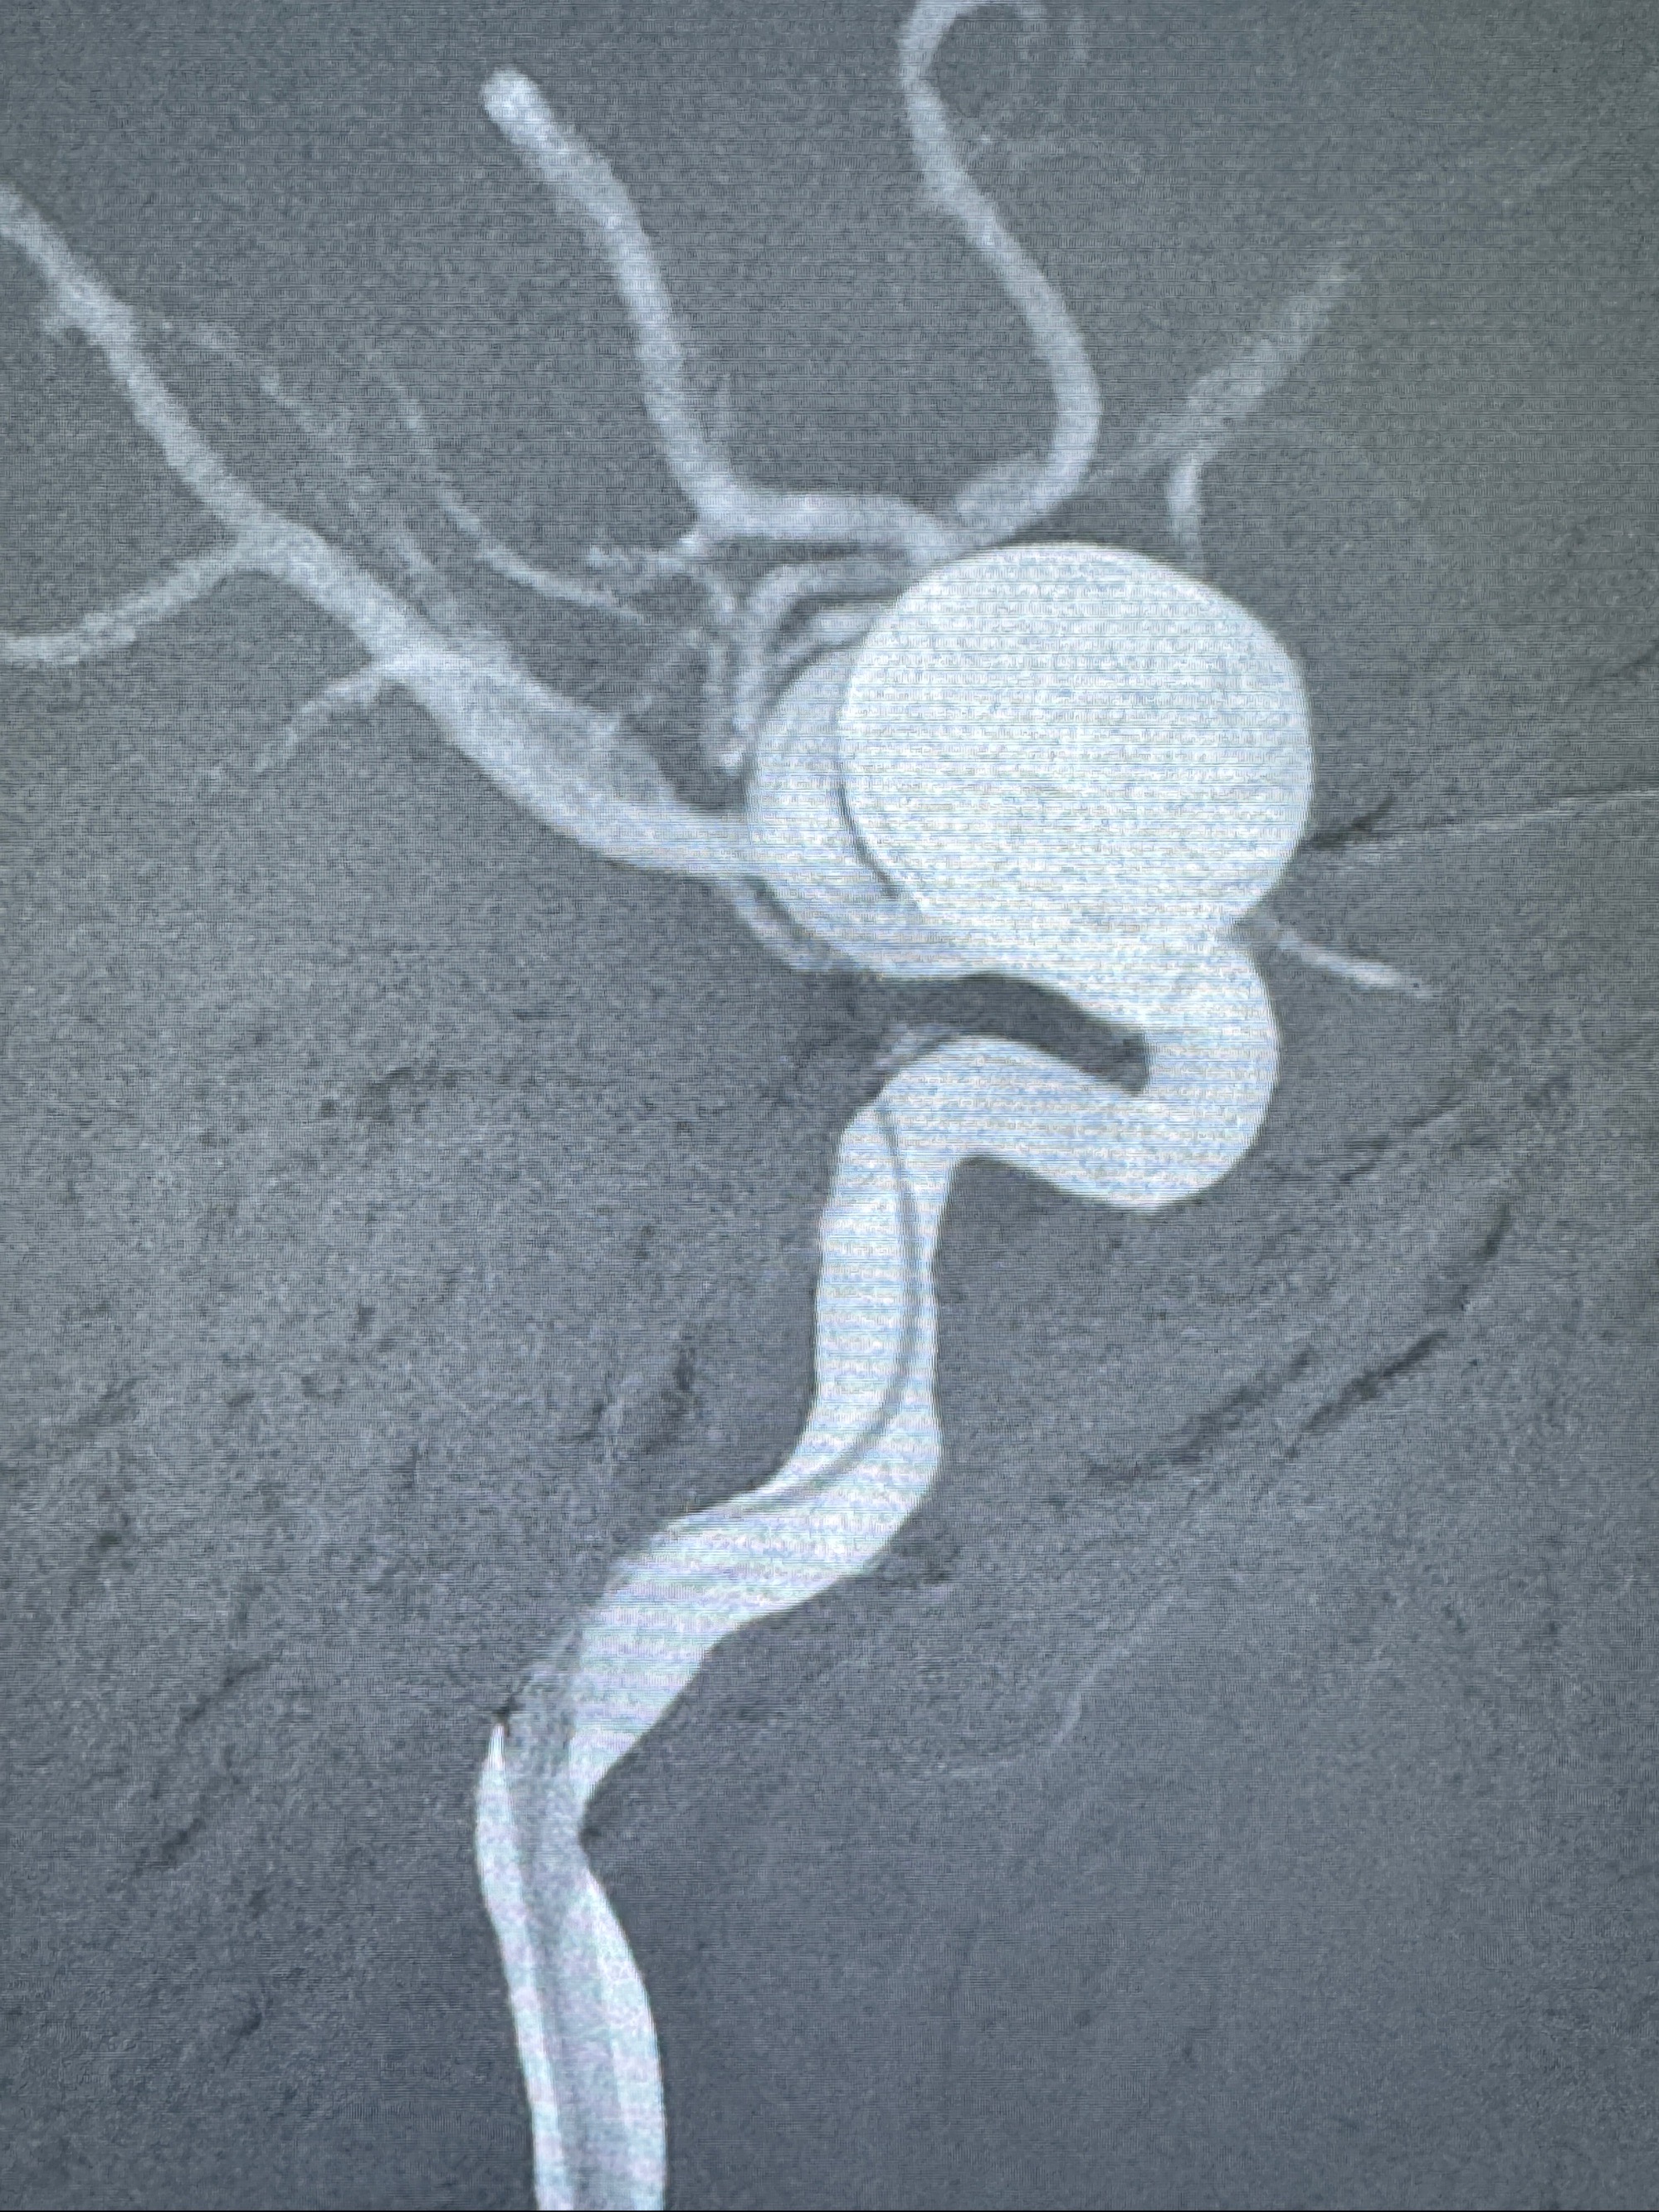

旋转3D展示动脉瘤局部的血管构筑

测量动脉瘤的大小:16*13.8*7.6mm大小,较原先变大,考虑双抗后瘤内血栓溶解可能

观察动脉瘤腔内的血流动力学情况